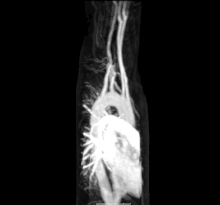

Other more invasive means can also be used. A cannula or catheter inserted into an artery may be used to measure pulse pressure or pulmonary wedge pressures. Angiography, which involves injecting a dye into an artery to visualise an arterial tree, can be used in the heart (coronary angiography) or brain. At the same time as the arteries are visualised, blockages or narrowings may be fixed through the insertion of stents, and active bleeds may be managed by the insertion of coils. An MRI may be used to image arteries, called an MRI angiogram. For evaluation of the blood supply to the lungs a CT pulmonary angiogram may be used.